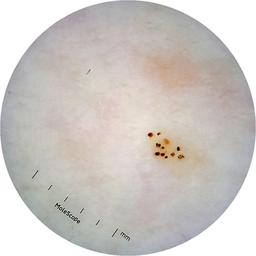

ISIC_6363669

IP_1322385

IL_2591344

acquisition_day 264

age_approx 65

anatom_site_1 Trunk

anatom_site_2 Anterior trunk

anatom_site_general anterior torso

diagnosis_1 Benign

diagnosis_confirm_type single image expert consensus

image_type dermoscopic